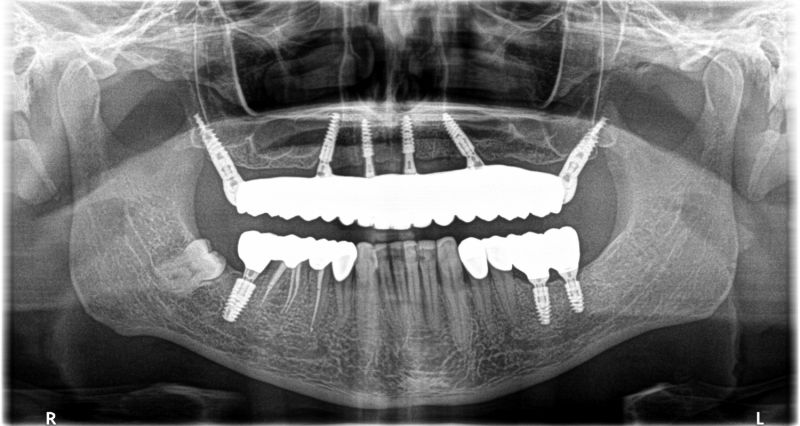

Wykonana praca protetyczna:

- most pełnołukowy na sześciu implantach

- korony na zęby własne w łuku dolnym

- korony na implantach w miejscach braków zębów

- odbudowa flow-injection zębów dolnych przednich